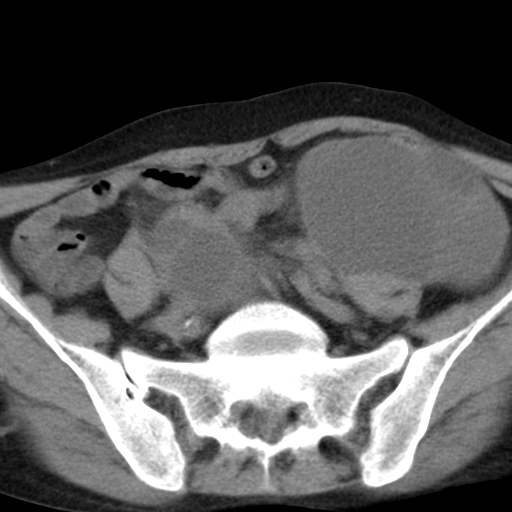

女,70,腹部间断性胀痛三月余

子宫宫腔及双侧附件积液,原因?

考虑卵巢囊腺瘤,不排除囊腺癌。

考虑卵巢囊腺瘤或囊腺癌。实质成分太多,考虑后者可能性大.

年龄较大还是恶性可能大,不排除库肯勃瘤

双侧卵巢粘液性囊腺癌,不多赘述。

考虑卵巢囊腺瘤;囊腺癌不能排除(理由:病人年龄较大,病灶外形欠规整、囊实相间,实性成分较多均支持囊腺癌)。要是能听听九目段老师的点评就好了!

年龄较大,囊实相间,实性成分较多均支持囊腺癌。

考虑囊腺癌,子宫病变不能排除吧,建议mri检查。